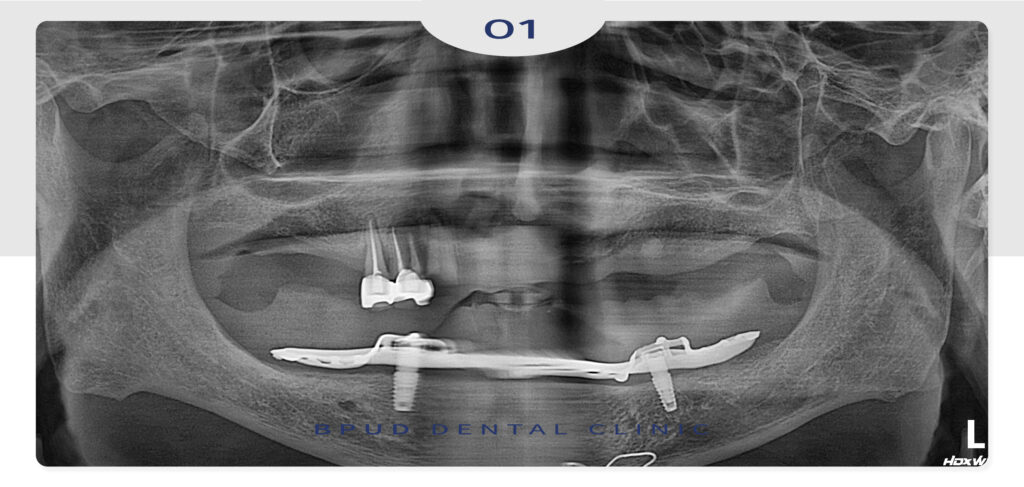

오랜 기간 틀니의 사용으로 치조골 흡수가

매우 심한 편이셨지만 안정적으로 식립과

최종 보철물까지 마친 모습입니다.

전체적으로 뼈이식술을 시행하여

인공치근이 뼈에 고정이 잘 되어

바로 힐링 어버트먼트를 연결하여

1차, 2차 수술을 동시에 진행하였습니다.